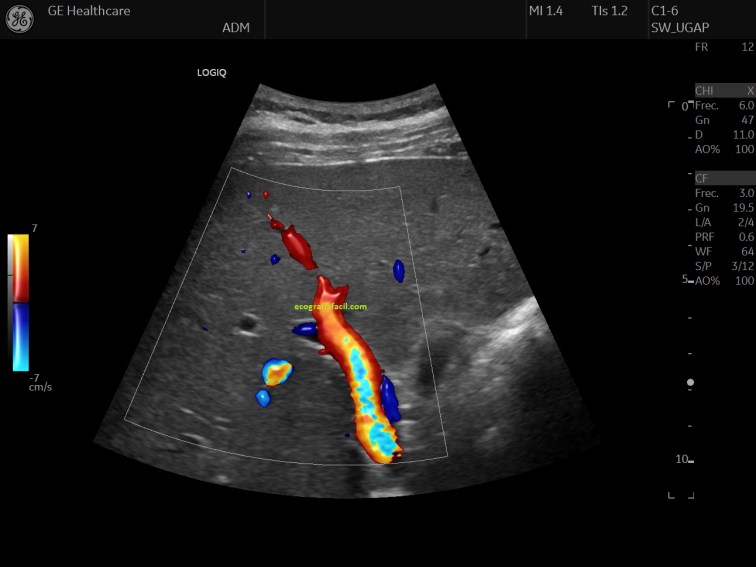

Esta semana he tenido la suerte de probar uno de estos equipos, el Logiq E10 de Ge. Me ha sorprendido enórmemente porque la evolución es sustancialmente mejor que los equipos más modernos que había tenido la oportunidad de probar. Son muchos los recursos que posee este equipo, Inteligencia Artificial, Fusión…ya os iré contando más adelante este tipo de avances, pero hoy quiero contarte algo…me sorprendió los nuevos «doppler», y me explico…En los modos de trabajo tenemos el modo 2D, Doppler Color, Power Doppler y luego el Doppler pulsado para hacer registros, bien los nuevos equipos viene con una evolución en este ámbito que me gustaría contarte.

La imagen 7 es un submodo de power doppler para capturar el flujo de vasos pequeños muy lento. Esta tecnología mejora la visualización de los vasos muy pequeños, es ideal para estudios tendinosos, ideal para tendinosis y estudio de regiones muy pequeñas, procesos patológicos articulares, en fin, es un gran avance para estudios de ecografía muscular y otros estudios que necesitan visualización de pequeños vasos, por ejemplo en transplante renal, ecografía testicular y otros. En este submodo de trabajo podemos individualizar el vaso sin ver el tejido que lo rodea o tenerlo visible a nuestro gusto